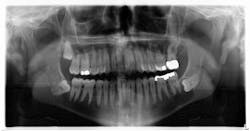

A healthy, 38-year-old male presented to the office for a comprehensive exam. His blood pressure was within normal limits, and no medications were being taken. Bitewing radiographs were taken, and it was noted that there was a cystlike lesion on what appeared to be a mesial impaction of no. 17. A panoramic radiograph indeed revealed a large, radiolucent/cystlike lesion surrounding a mesial/inferior-positioned no. 17. The widest point of the cyst measured approximately 3 cm. The patient reported knowing about the lesion but was not inclined to have it removed because it was not bothering him. The area was not tender to palpation; tooth no. 18 had normal pocketing and tested normal to cold, percussion, and bite.